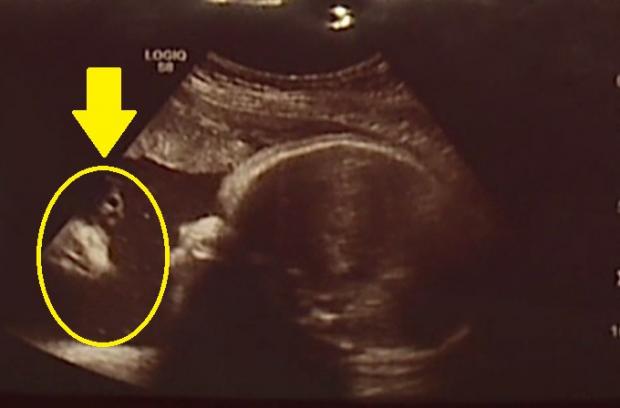

Doi viitori părinți americani au fost extrem de surprinși când, în urma unei vizite la medic pentru o ecografie, au descoperit un detaliu deosebit pe ecranul dispozitivului medical.

Undeva, în stânga, se putea observa chipul lui Iisus. Cei doi părinți afirmă că nu sunt prea religioși însă apariția i-a emoționat destul de tare, potrivit BBC.com.

“Când l-am văzut, am plâns, nu-mi venea să cred”, a spus tatăl.